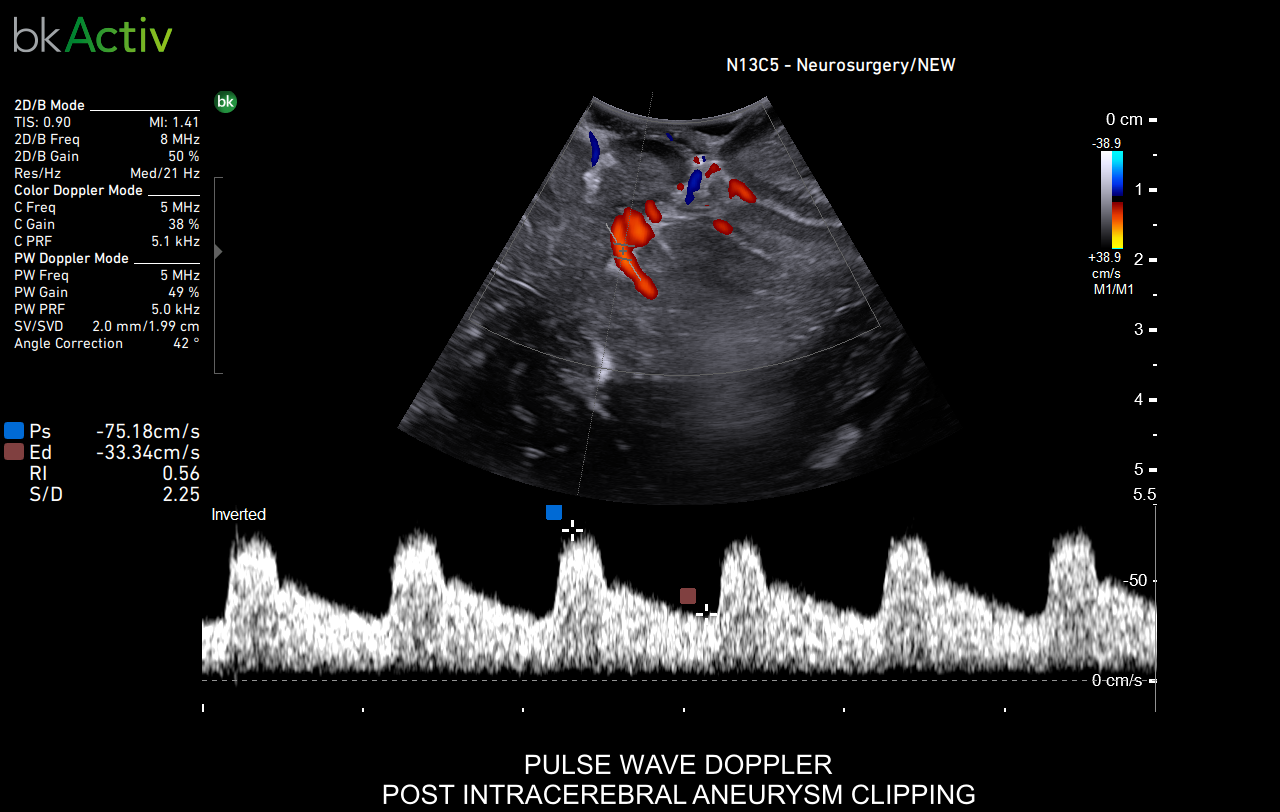

Neurosurgery and Spine

Enhanced Visualization

Improved algorithms that automatically allow uniform image resolution, greater details around lesion borders and at larger depths, and enhanced penetration, spatial resolution, and near field image quality.